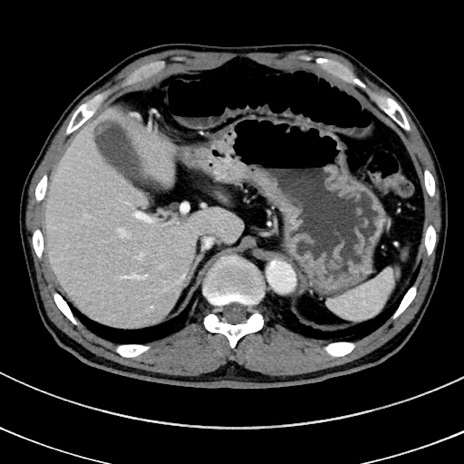

症例8(横断像)

【症例】 60歳代男性

【主訴】 黒色吐物

【現病歴】 4日前から嘔気自覚、2日前の朝食後にも嘔気あり、自分で手で嘔吐反射起こし嘔吐したところ血が混ざっていたため受診。

【既往歴】 5年前汎発性腹膜炎を伴う急性虫垂炎で手術、高血圧、前立腺肥大症、高脂血症

【身体所見】 腹部正中に手術癩痕あり 腹部平坦・軟圧痛なし膨満感あり

【データ】WBC 8400、CRP 4.54